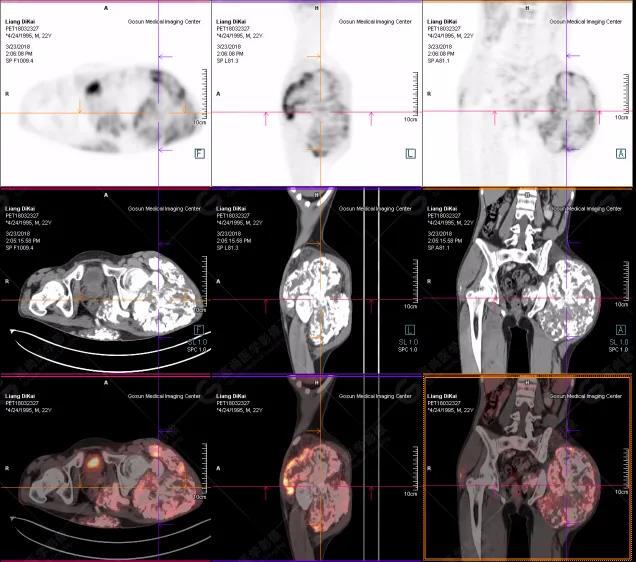

本中心PET/CT提示

1.右肘關(guān)節(jié)周圍、骶尾部皮下、雙側(cè)臀部、盆腔左側(cè)壁及左側(cè)大腿根部肌肉、肌間隙多發(fā)結(jié)節(jié)狀、片塊狀及不規(guī)則巨塊狀高密度鈣化灶,伴代謝不均勻輕度增高,考慮為鈣質(zhì)沉著癥;

2.甲狀腺雙葉后方多發(fā)(右2個,左1個)小結(jié)節(jié)狀軟組織影,部分代謝輕度增高,多考慮為甲狀旁腺腺瘤。